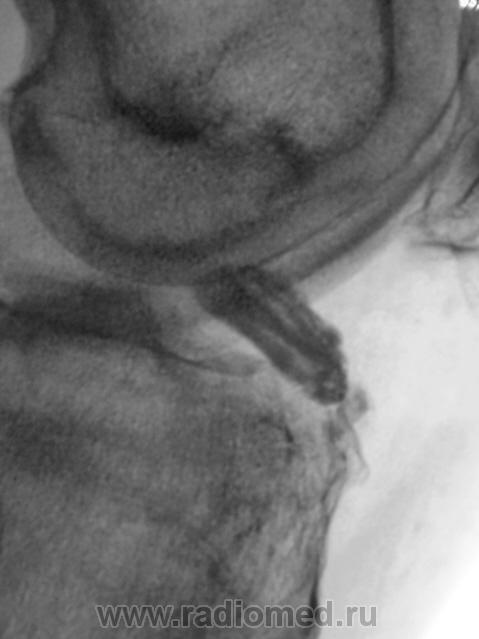

Пациент направлен в рентгеновский кабинет врачом хирургом для рентгенографии коленного сустава. Пациента в течение 2-х лет беспокоят боли в коленном суставе "Тупого характера". Хирургом выставлен диагноз - "Деформирующий артроз". Произведены рентгенограммы.

Свободное внутрисуставное тело.

Согласен по поводу мениска -- вероятно, фрагмент медиального. И обратите внимание на мелкую тень с латеральной стороны -- то ли ещё одно свободное тело, то ли обызвествление в толще латерального мениска.

upd: перечитал пост -- засомневался: неужели свободное тело за два года дало только "тупые боли"?